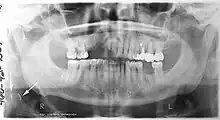

Panoramic radiograph

A dental panoramic radiograph, showing the maxilla and mandible, all the teeth including the "wisdom teeth," the frontal and maxillary sinuses, the nasal cavity and the temporomandibular joint and other near by head and neck anatomy.